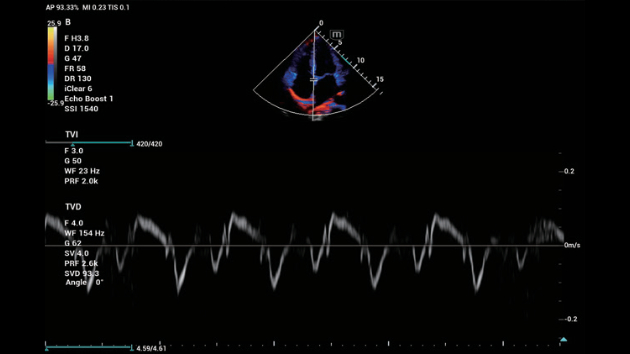

N?o importa se sua rotina ÃĐ em hospitais, clÃnicas ou se vocÊ estÃĄ aprimorando habilidades em Imagem Geral, SaÚde da Mulher ou na ÃĄrea Cardiovascular; vocÊ encontrarÃĄ ferramentas altamente poderosas disponÃveis para manter-se na vanguarda.

Solu??es abrangentes de imagens com tecnologia ZST+

A plataforma ZST+ ÃĐ uma inova??o extraordinÃĄria, representando a evolu??o do ultrassom. Transformando as mÃĐtricas de ultrassom: da forma??o convencional do feixe ao processamento baseado em dados de canais. Supera a limita??o de compensa??o tradicional entre resolu??o espacial, resolu??o temporal e uniformidade de tecido, oferecendo qualidade de imagem excepcional para solu??es de imagem infinitas com melhorias inigualÃĄveis.